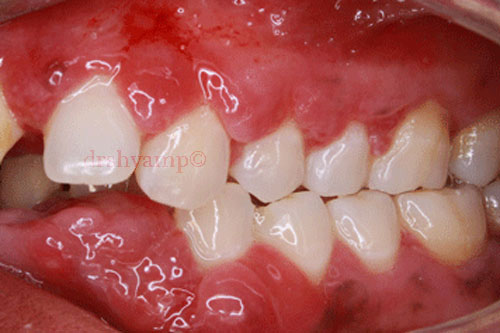

Prgenancy Gingivitis